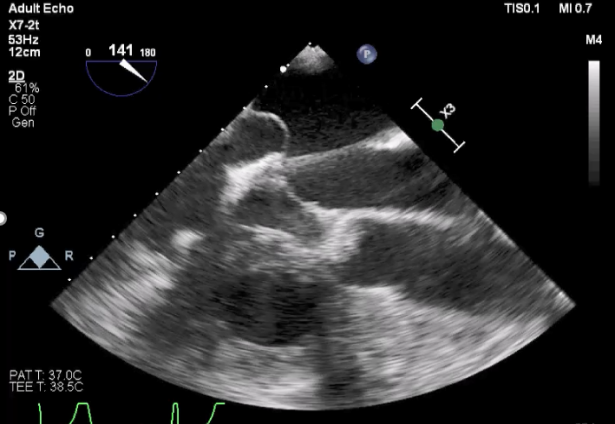

术前TEE

TEE短轴脱垂区域显示(P2、P3区大范围脱垂)

TEE短轴脱垂区域显示(color,血流来源于P2、P3区)

三维超声心动图显示第一枚XTR夹子释放,残余返流主要位于外侧

三维超声心动图显示第二枚XTR夹子释放